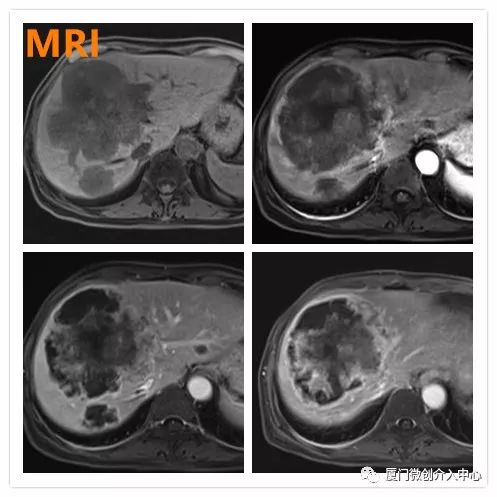

复查MRI显示病灶大部分坏死

复查PET-CT亦提示病灶大部分已无活性,仅病灶下缘残存少许活性,后续行局部放射性粒子植入控制